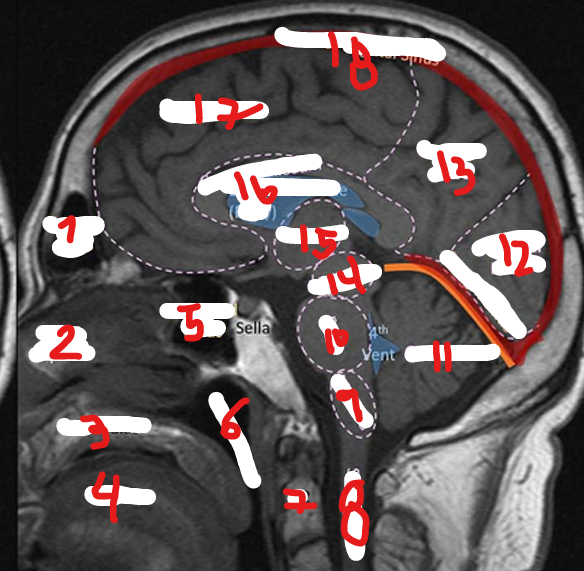

FRONTAL LOBE

1

<p>1</p>

7

New cards

PARIETAL LOBE

2

<p>2</p>

8

TEMPORAL LOBE

3

<p>3</p>

9

INSULA

4

<p>4</p>

10

OCCIPITAL LOBE

5

<p>5</p>

11

CEREBRUM

6

<p>6</p>

FRONTAL SINUS

39

NASAL SEPTUM

40

HARD PALATE

41

TONGUE

42

SPHENOID SINUS

43

NASOPHARNYX

17

<p>17</p>

C2

<p>7</p>

46

SPINAL CHORD

<p>8</p>

47

MEDULLA

<p>9</p>

48

PONS

<p>10</p>

49

CEREBELLUM

<p>11</p>

50

12

<p>12</p>

51

13

<p>13</p>

52

MIDBRAIN

14

<p>14</p>

53

THALAMUS

15

<p>15</p>

54

CORPUS CALLOSUM

16

<p>16</p>

55

SUPERIOR SAGITAL SINUS

18

<p>18</p>